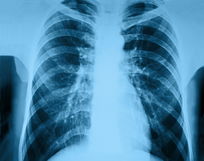

Imagem ilustrativa número 1

Além disso, o médico também pode pedir alguns exames complementares, como raio-X, exame de sangue, teste de escarro, exame que é feito ao tossir profundamente e expelir o muco, para que sejam avaliados os tipos de microrganismos e oximetria, que é um aparelho para medir a quantidade de oxigênio no sangue.